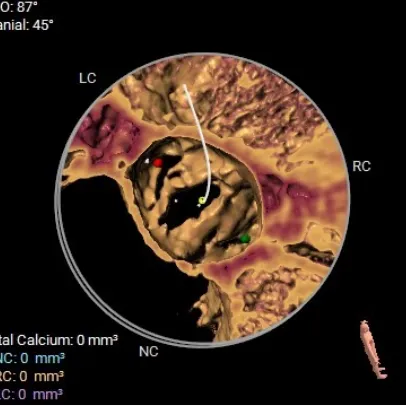

术前CT评估:TYPE 0型二叶瓣,瓣叶肥厚,前后交界粘连,瓣叶无明显钙化,双冠异窦,左冠开口高度约16.6mm,右冠开口高度约16.7mm。法式窦结构小,STJ高度约21.6mm,直径约24.4mm,升主动脉未见明显增宽,心脏角度约42°,左室大小尚可,心尖部可见局部心肌薄弱。

TYPE 0型二叶瓣,瓣叶肥厚,前后交界粘连,瓣叶无明显钙化

钙化积分:0mm³,无钙化